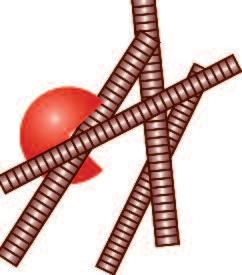

Un altro processo durante il quale ha luogo la digestione del collagene è in caso di infezione. La difesa del corpo contro gli invasori (microbi) è assicurata dai globuli bianchi presenti nel sangue. Diversi sottogruppi di globuli bianchi svolgono funzioni specifiche del sistema immunitario, meccanismo di “difesa” a livello cellulare.

Particolarmente importanti sono i macrofagi, che possono ‘mangiare’ e digerire gli invasori. Forme immature di queste cellule, chiamate monociti, possono raggiungere ogni parte del corpo attraverso il flusso sanguigno. Se l‘infezione avviene nei polmoni, il corpo secerne ’sostanze di emergenza' che attraggono i monociti nel luogo dell’infezione.

In caso di infezione polmonare, i globuli bianchi, che giungono con il flusso del sangue, attraversano la parete dei vasi sanguigni, piccoli capillari polmonari, per trasferirsi poi nel tessuto polmonare, con l'aiuto di enzimi che dissolvono il collagene. Per raggiungere il sito dell’infezione nei polmoni (ad esempio, batteri o virus), i globuli bianchi devono essere in grado di migrare attraverso il tessuto polmonare Per far ciò, utilizzano lo stesso meccanismo per sciogliere il collagene, allentando il denso tessuto connettivo circostante e spostandosi attraverso il tessuto in modo molto simile descritto nel paragrafo precedente, la produzione di collagenasi agisce come un machete usato per aprire un varco attraverso la giungla.

Subito dopo che i globuli bianchi sono migrati e hanno raggiunto il punto nel quale é in corso un’infezione ,il tessuto connettivo si richiude, utilizzando meccanismi che neutralizzano gli enzimi e riparano i tessuti.

Questa riparazione è garantita da un’adeguata disponibilità di fattori neutralizzanti le collagenasi, ‘pacman’, provvedendo alla produzione di nuove molecole di collagene.

Es.: Infezione polmonare

I globuli bianchi (il sistema di difesa del nostro corpo) lasciano un piccolo vaso dei polmoni per spostarsi con l’aiuto delle collagenasi nel focolaio dell’infezione

Subito dopo la migrazione dei globuli bianchi si blocca la produzione delle collagenasi e si ripara il tessuto connettivo.

In normali condizioni fisiologiche i globuli bianchi utilizzano le collagenasi per una durata di tempo ben preciso, determinato dalla funzione (difesa immunitaria) che svolgono.

Ab) Le cellule bianche del sangue lasciano il flusso sanguigno e, con l‘aiuto di enzimi che digeriscono il collagene, penetrano all'interno della parete dei vasi sanguigni.

a) Un globulo bianco dal flusso di sangue (area bianca) si attacca al rivestimento delle cellule (cellule endoteliali) della parete dei vasi sanguigni.

Cd) Le cellule bianche del sangue hanno iniziato la loro migrazione attraverso il tessuto connettivo che ora ne è completamente circondato

c) I globuli bianchi ora hanno abbandonato completamente il flusso sanguigno e la parete dei vasi sanguigni è ben chiusa alle loro spalle.